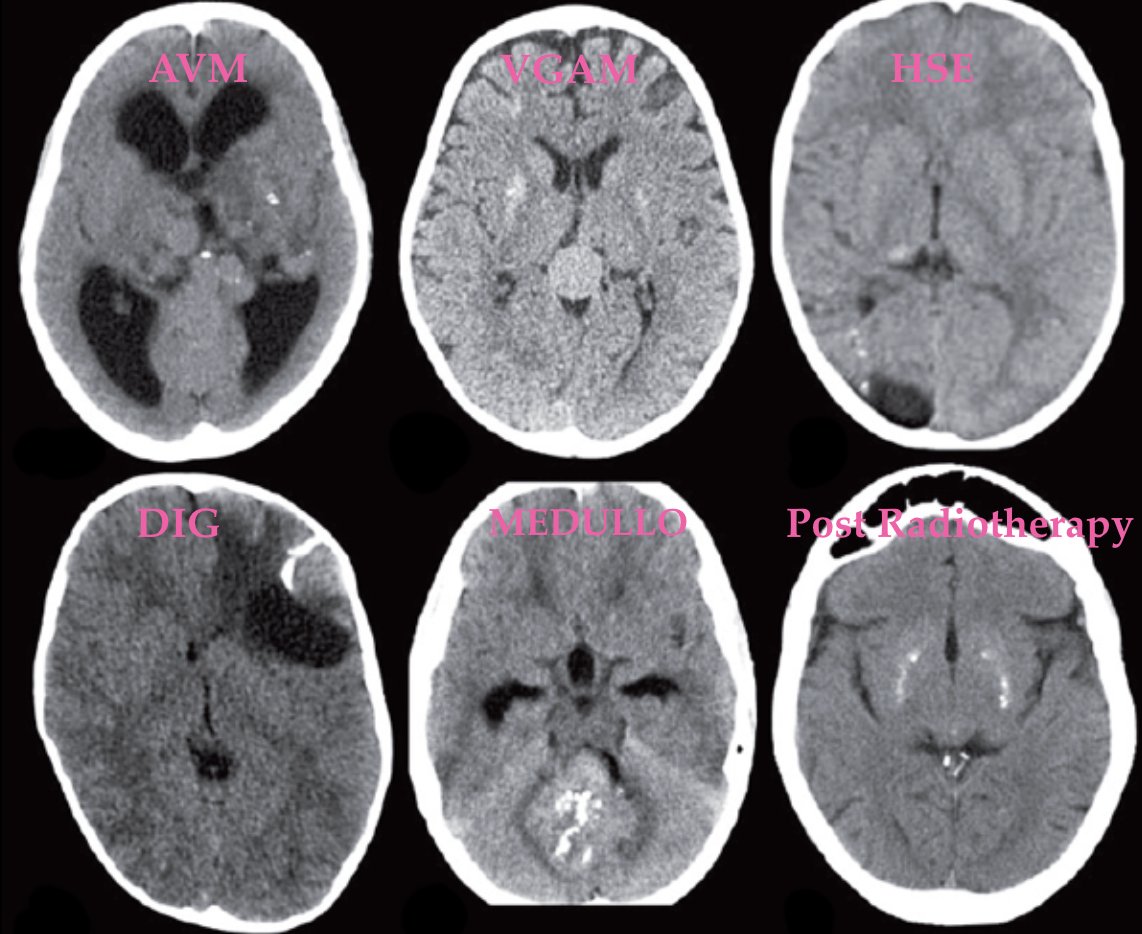

Intracranial calcifications in children, supplementary to AJNRcow submitted by Dr. Rahul Lakshmanan

@shmayyn https://onlinelibrary.wiley.com/doi/full/10.1111/dmcn.12359 … https://onlinelibrary.wiley.com/doi/epdf/10.1111/j.1469-8749.2012.04437.x …#Pedineurorad#neurorad#radres#radiology https://twitter.com/TheAJNR/status/1212846238644756480 …pic.twitter.com/gnToHOpgn8

Hvala. Twitter će to iskoristiti za poboljšanje vaše vremenske crte. PoništiPoništi -